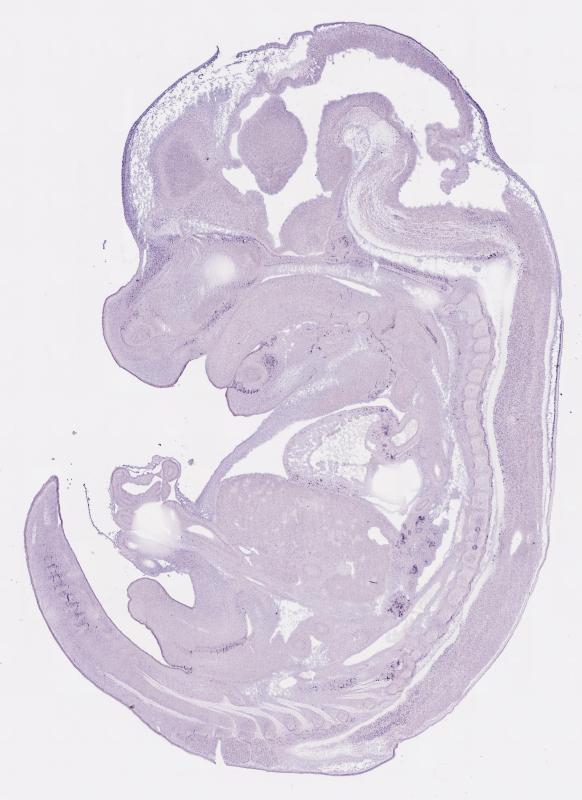

EH698; Specimen C2424:

embryonic day 14.5